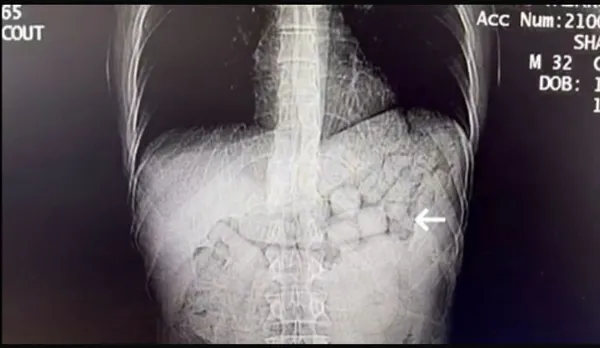

Bahse konu şahısların çekilen tomografi görüntülerinde, mide ve bağırsak bölümlerinde yabancı cisimlere rastlandı. Yaklaşık 3 gün süren kontroller sonucunda yabancı uruklu uyuşturucu taciri iki kişinin mide ve bağırsağından 91 kapsül halinde 807,15 gram Metamfetamin maddesi ele geçirildi.